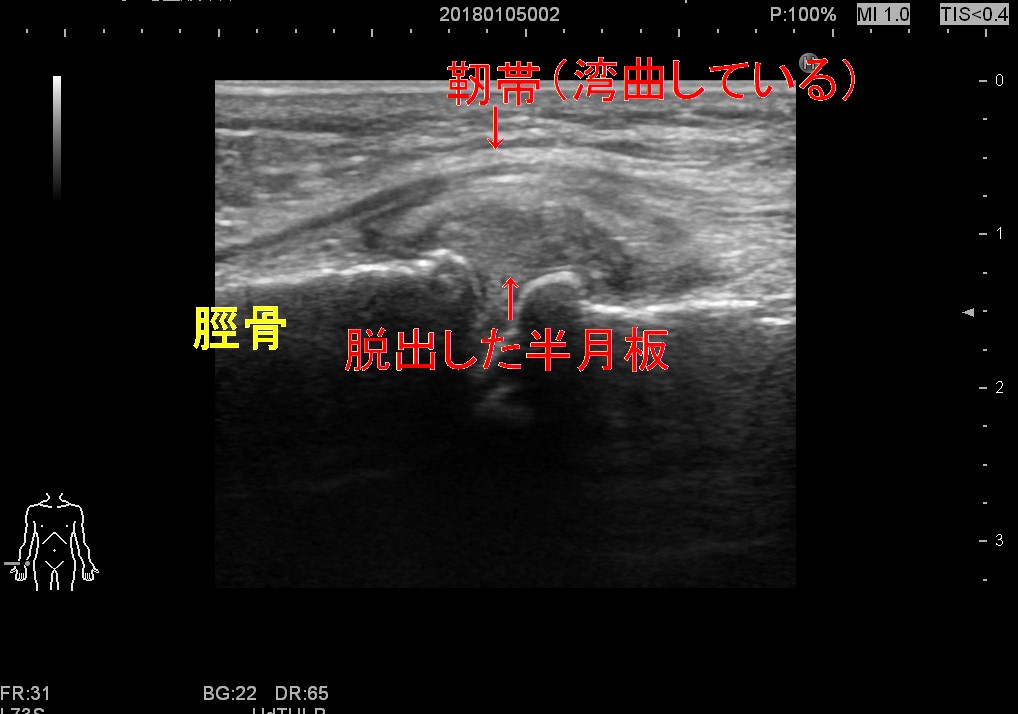

よくある膝の痛み

膝の内側、外側、前上方、前下方、裏側その他いろいろ痛い所は千差万別です

確かに骨や半月板の悪い方も見えます。

テレビや雑誌情報はたまた巷でも半月板が悪いんだ。もっとひどいと

軟骨がすり減ってるんだと一蹴されて終わりの患者さんも大勢います。

でも痛みの原因がそれだけではないのは明白。また民間療法としていろいろな

マッサージ、ストレッチ、トレーニングもあります。その中には有効なものが

あります。痛んだ半月板やすり減った軟骨が治るはずもありません。

ではなぜ有効か?

理由としては半月板の傷や軟骨のすり減りが原因ではない多くの膝痛の患者さんが

いるからにほかなりません。以下の画像は皆さん膝の内側の痛みの方のエコー画像です。

ぼろぼろに痛んだもの、脱出して盛り上がってしまったものもありますが

一見して正常な半月板の人も痛みを訴えます。

痛みの原因は湾曲圧排された靭帯、そして大腿部や下腿の筋肉の柔軟性の低下のため

間接的に靭帯に負担がかかっているものと推察しています。

もちろん骨病変や内側半月板後角断裂など重症の骨軟骨病変の方も少数ながらいらっしゃいます

仮に変性がなければもちろん、あっても大腿、下腿筋の柔軟性向上は痛みを劇的に

緩和することもありますので適切な診断のもと自宅や病院などでリハビリを行うことを

お勧めしたいですね。ただ中には疼痛が重度の方は素早く痛みから解放することも

重要です。靭帯/半月板リリースが有効な方が多い印象です。